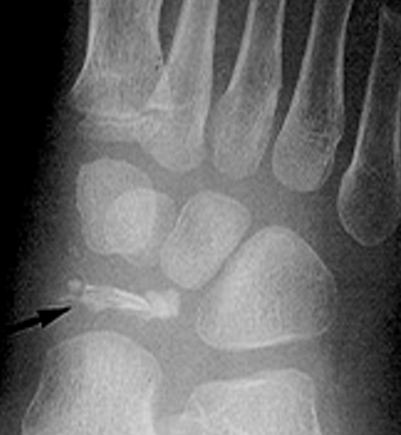

Kohler’s Disease - Classification

traumatic

Kohler’s Disease - Etiology

trauma - usually compression type injury

avascular necrosis of navicular bone

Kohler’s Disease - Pathogenesis

compression and/or injury during development phase, thus predom affects children 3-7 yrs (males)

Kohler’s Disease - Radiographic Appearance

patchy and/or homogenic sclerosis (increased density)

severe cases bone collapses and fragments

abnormal architecture evident into adulthood